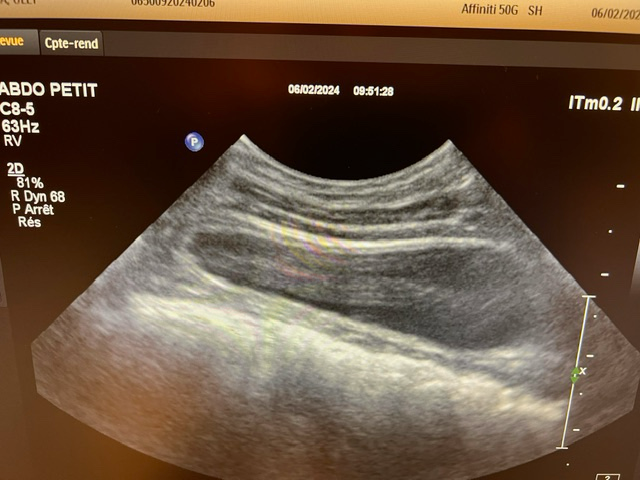

흉부 엑스레이상에서는 교통사고와 관련한 특별한 이상이 관찰되지 않습니다.

초음파 검사의 경우 초음파를 직접 본 사람이 아니면 찍어놓은 사진으로는 아무런 판단을 할 수 없고 해서도 안됩니다.

주치의의 판단이 가장 정확한 판단이겠으나 지현형으로 장기 손상이 일어나는 경우가 종종 있기 때문에 증상이 지속된다면 복부 초음파 검사를 다시 받아볼 필요가 있어 보입니다.